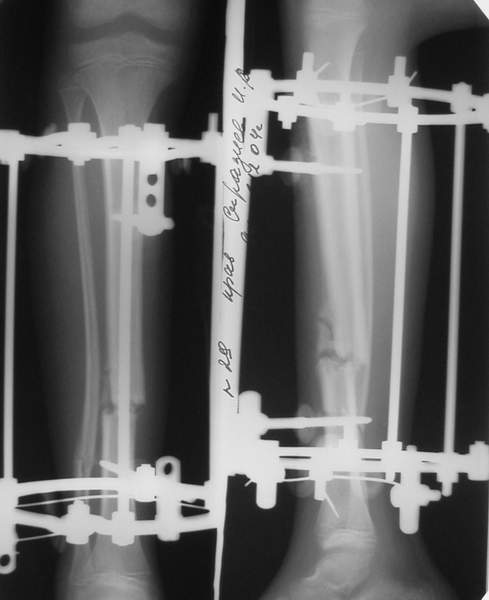

3b

3c

В аттачте № 3 - один из примеров полукольцевого аппарат...

Это уже я баловался.

Итог? Работы больше (по времени и

интраоп "подгонке"), срастается также, а особого преимущества по сравнению с

"чиста" кольцевым (вес, удобство ношения и пр.) - я, по крайней мере,

не нашел.

Теперь не балуюсь.

МТ мы используем, конечно, не только на голени. В прилагаемом примере у парня при поступлении была наружная ротация 40 гр. и "полумертвый" коленный сустав. Можно был бы, конечно, до конца использовать полную компоновку. Но для того он и есть метод выбора.